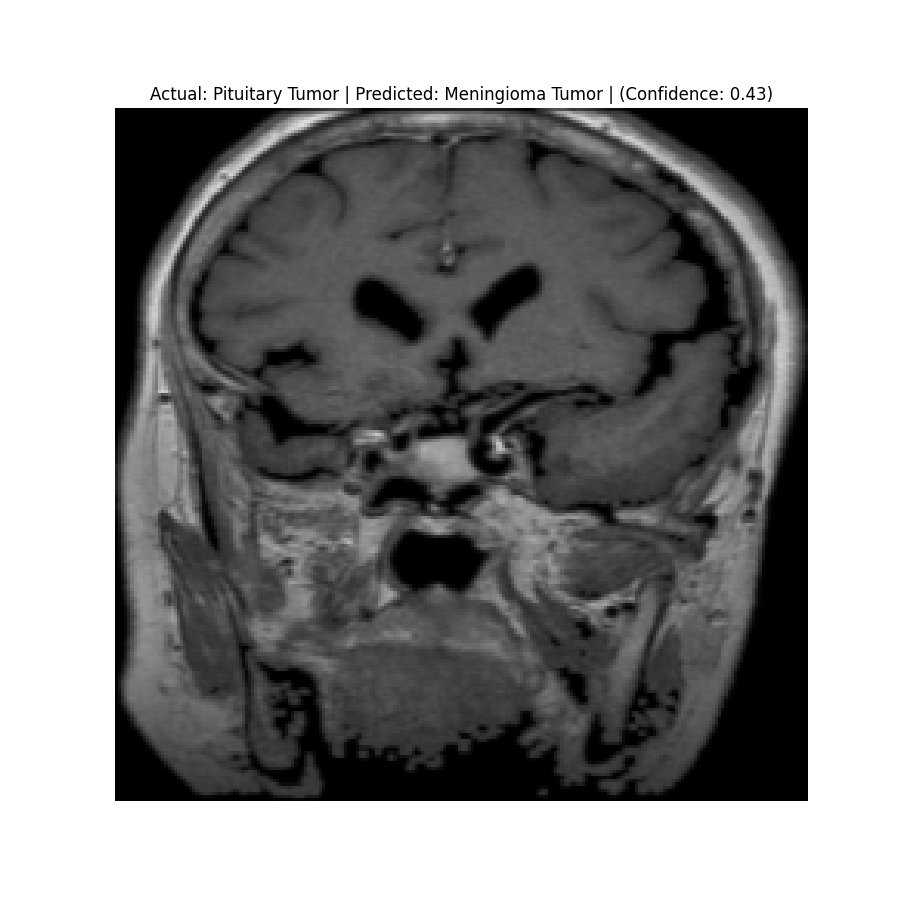

Check the predictions in the predictions folder. Below are some sample results:

![]() Actual: Pituitary Tumor Predicted: Pituitary Tumor (Confidence: 0.51) | ![]() Actual: Pituitary Tumor Predicted: Meningioma Tumor (Confidence: 0.43) |